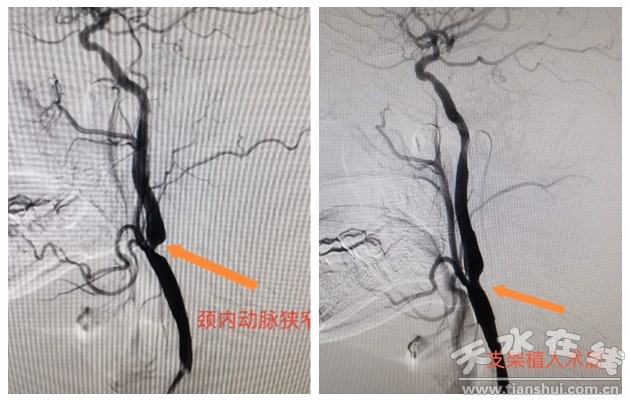

近日,天水市第四人民医院介入医学科为一位56岁患者成功实施了颈内动脉支架植入。患者为中年男性,因“高血压,伴头晕”收住心血管内科,既往有高血压、糖尿病、高脂血症病史。入院后完善相关检查,颈部彩超及头颈部CTA结果提示右侧颈内动脉全段闭塞,左侧颈内动脉起始90%狭窄,远端颅内血流受到一定程度的限制。

经心内科团队与介入医学科团队反复讨论,仔细评估,为患者进行左侧颈内动脉支架植入。首先使用栓子保护伞送至左颈内动脉远端进行保护,用球囊扩张导管对靶病变进行预扩张,然后将自膨式颈动脉支架在靶病变处释放,近端支架边缘跨越右颈内、颈外动脉开口,支架释放后血管造影显示,狭窄区血流通畅,远端血流恢复良好,支架植入成功。术后严密监测患者血压心率变化,患者一般情况良好,病情得到有效的控制和治疗,顺利出院。出院一周随访患者感觉良好,无特殊不适。